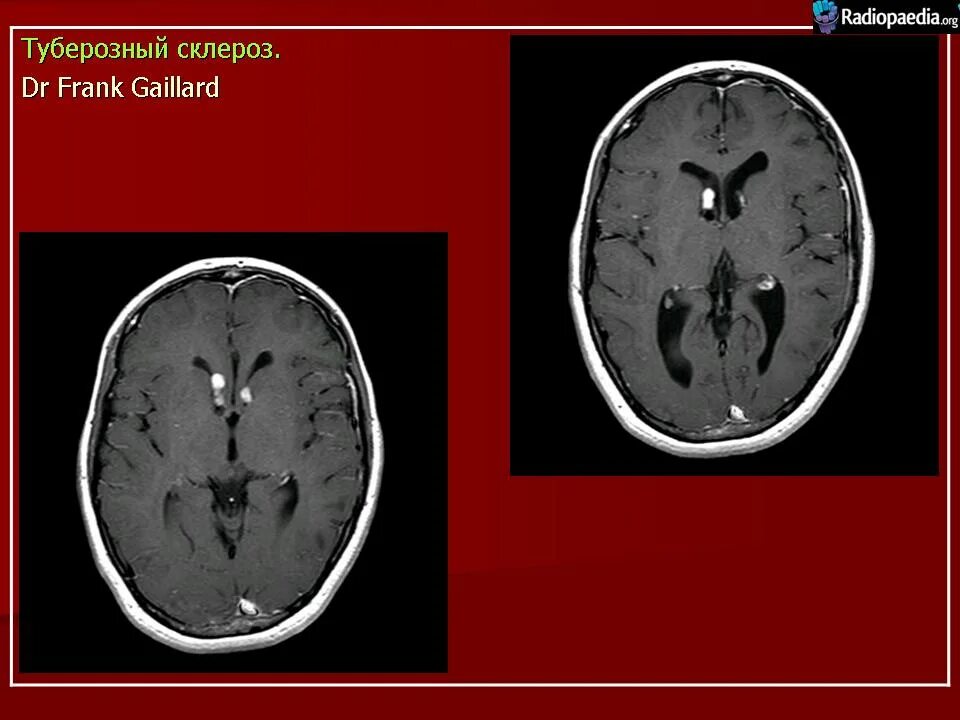

Туберкулезный склероз